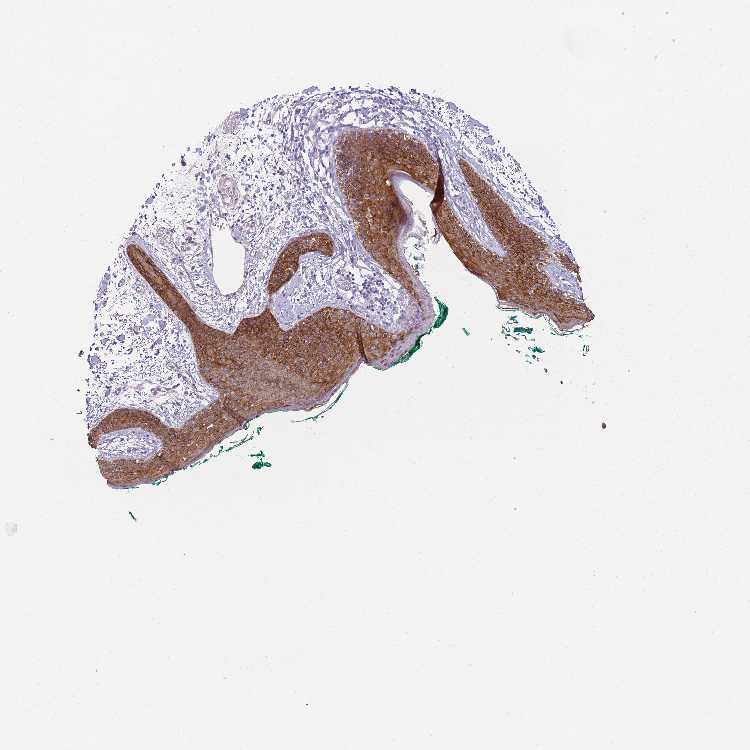

SKIN 2 - Antibody stainingi

Antibody staining in the annotated cell types in the current human tissue is reported as not detected, low, medium, or high, based on conventional immunohistochemistry profiling in selected tissues. This score is based on the combination of the staining intensity and fraction of stained cells.

Each image is clickable and will lead to virtual microscopy that enables deeper exploration of all samples and also displays staining intensity scores, fraction scores and subcellular localization as well as patient and tissue information for each sample.

Antibody HPA000497Antibody CAB004439Antibody CAB047331

Cells in basal layer --Medium

Cells in corneal layer --Not detected

Cells in granular layer --High

Cells in spinous layer --High

Endothelial cells --Medium

Epidermal cells HighHigh-

Extracellular matrix --Not detected

Fibrohistiocytic cells --Not detected

Langerhans cells --High

Lymphocytes --Not detected

Melanocytes --Medium

Vascular mural cells --Not detected